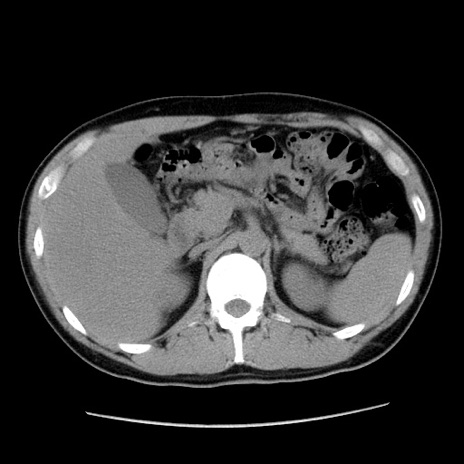

症例36(横断像)

【症例】20歳代 男性

【主訴】心窩部痛

【現病歴】今朝より上腹部痛あり。一旦軽快していたが再度出現したため救急要請。昨日夕に白身の魚を含む刺身を食べた。

【身体所見】BP 136/89mmHg、HR 74/min、BT 37.0℃、腹部:膨満、軟、心窩部に圧痛あり。反跳痛なし、筋性防御なし、腸雑音やや亢進あり。

【データ】WBC 17700、CRP 0.48